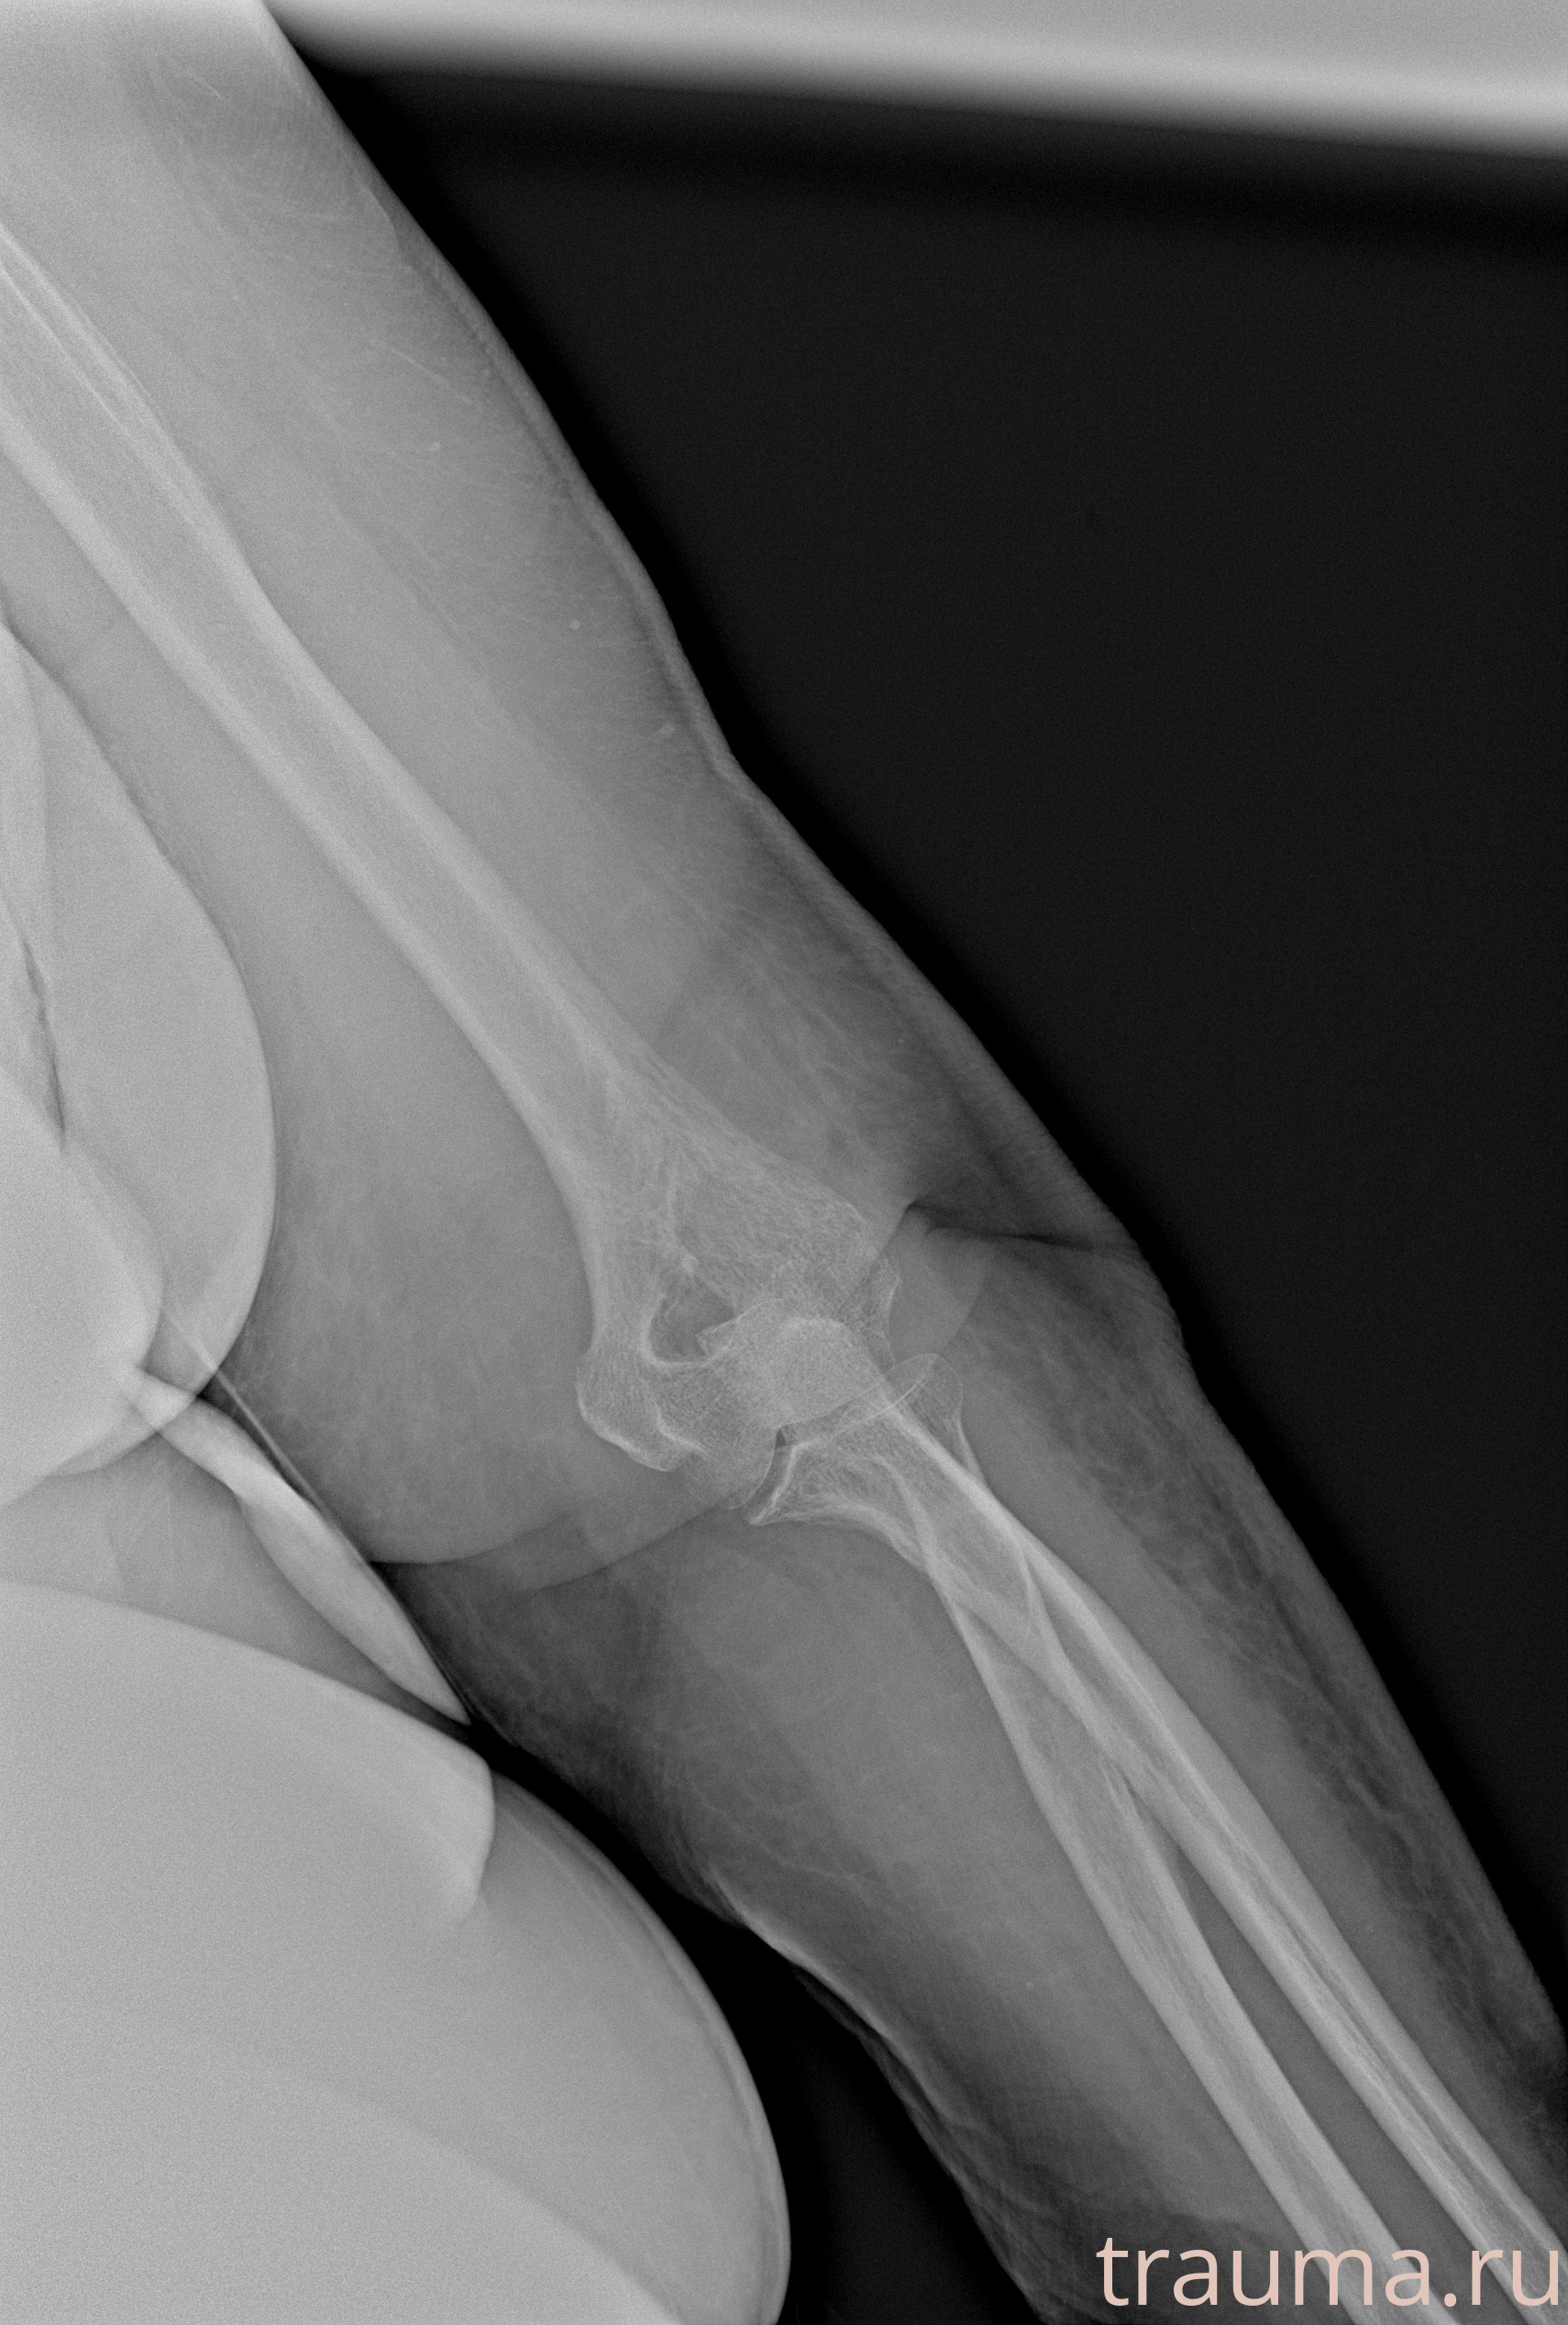

Рентген на дому: по вашему адресу приезжает врач-рентгенолог, травматолог-ортопед с мобильным рентгеновским аппаратом, проводит диагностику травмы или заболевания, делает необходимые рентгенограммы, дает рекомендации по дальнейшему лечению. Получить качественные снимки в домашних условиях возможно благодаря уникальной методике, разработанной МосРентген Центром для института  Склифосовского

при переломе шейки бедра и пневмонии от компании МосРентген Центр - партнера Института имени Склифосовского